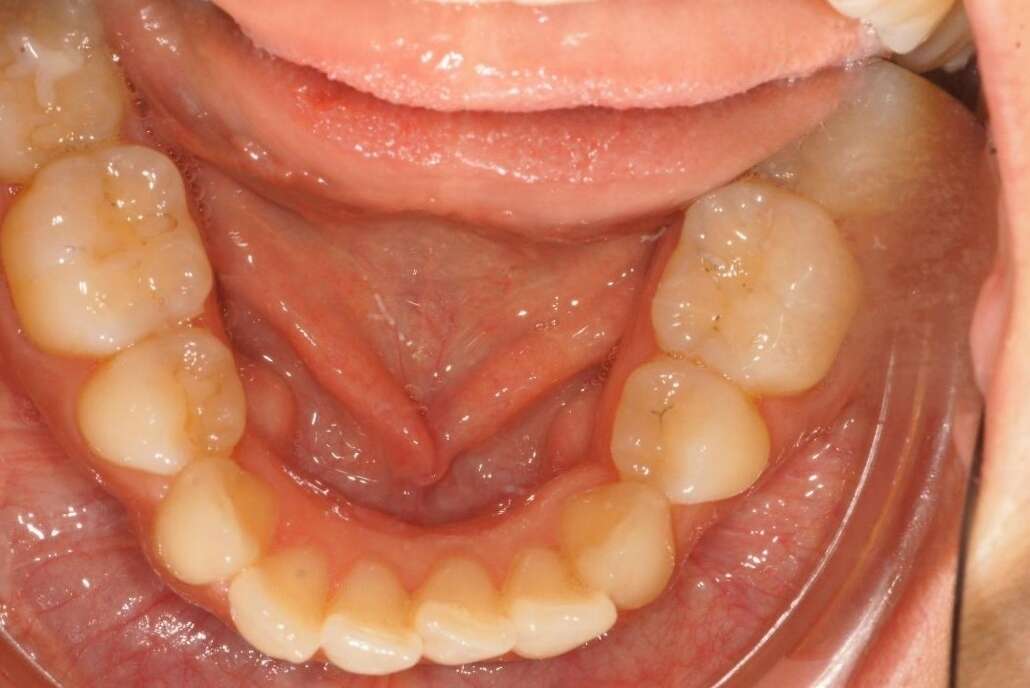

Reprise de récidive par gouttières

Début de traitement